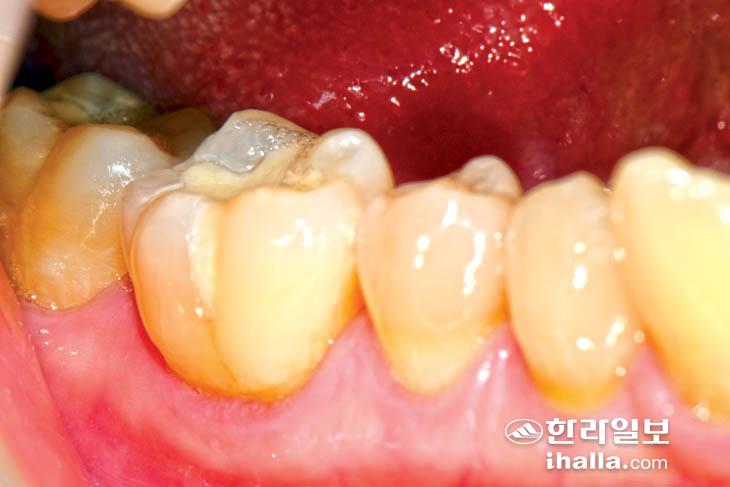

위의 사진은 91세 환자의 치아.

91세 고령의 환자이기에 이런 경우는 노화에 따라 자연적으로 진행된 마모라고 할 수 있다. 하지만 40~50대 환자의 치아가 이러한 마모소견을 보인다면 비 기능이상습관이 있는 것으로 짐작해 볼 수 있다.